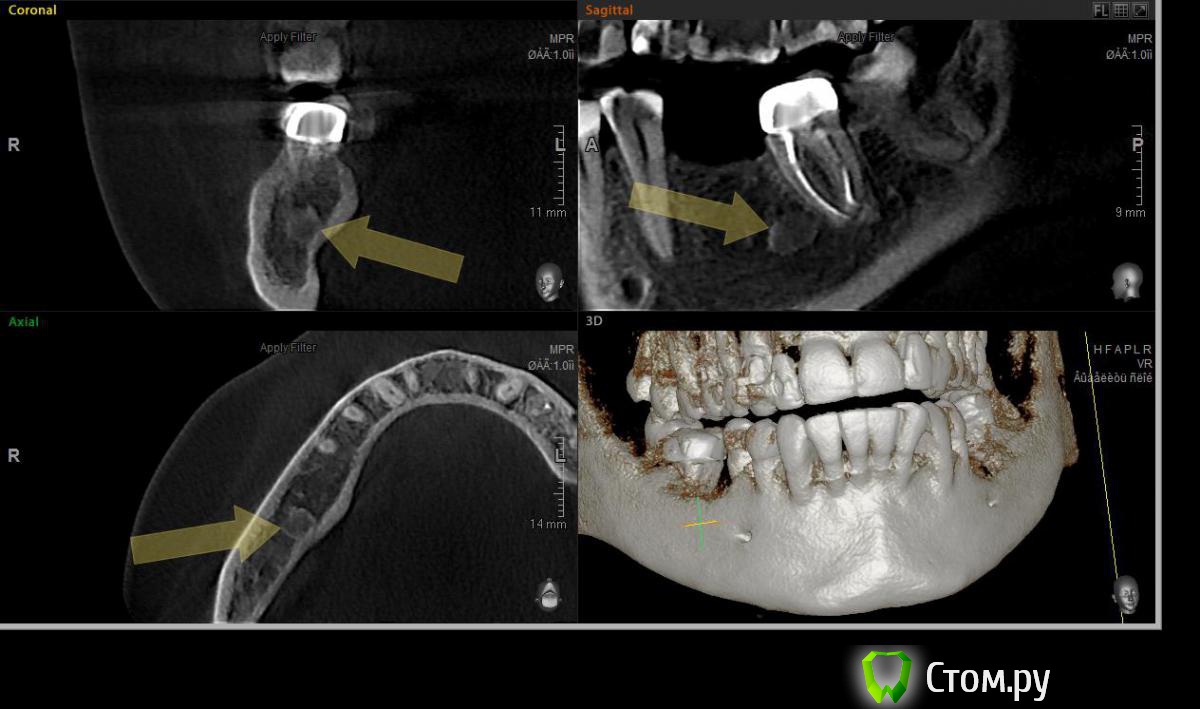

HSS Опубликовано 23 ноября, 2014 Поделиться Опубликовано 23 ноября, 2014 Добрый вечер, коллеги! При планировании имплантации в области 46 обнаружил неизвестное образование в области 46. На одной из проекций визуализируется, что-то наподобие свищевого хода в альвеолярном отростке, но на слизистой никаких изменений нет.Следовательно, вопрос, что это?Не будет ли проблем после установки имплантата? Ссылка на комментарий

kriokov Опубликовано 23 ноября, 2014 Поделиться Опубликовано 23 ноября, 2014 на остеому похоже, а на альвеолярном видимо кость так организовалась после удаления шестого Ссылка на комментарий

HSS Опубликовано 23 ноября, 2014 Автор Поделиться Опубликовано 23 ноября, 2014 на остеому похоже, а на альвеолярном видимо кость так организовалась после удаления шестогоЯ так понимаю, что остеома по соседству никакой опасности не несет, можно смело ставить? Ссылка на комментарий

zubnojvrach Опубликовано 26 ноября, 2014 Поделиться Опубликовано 26 ноября, 2014 я думал что это от резорцин-формалинового метода следы Ссылка на комментарий